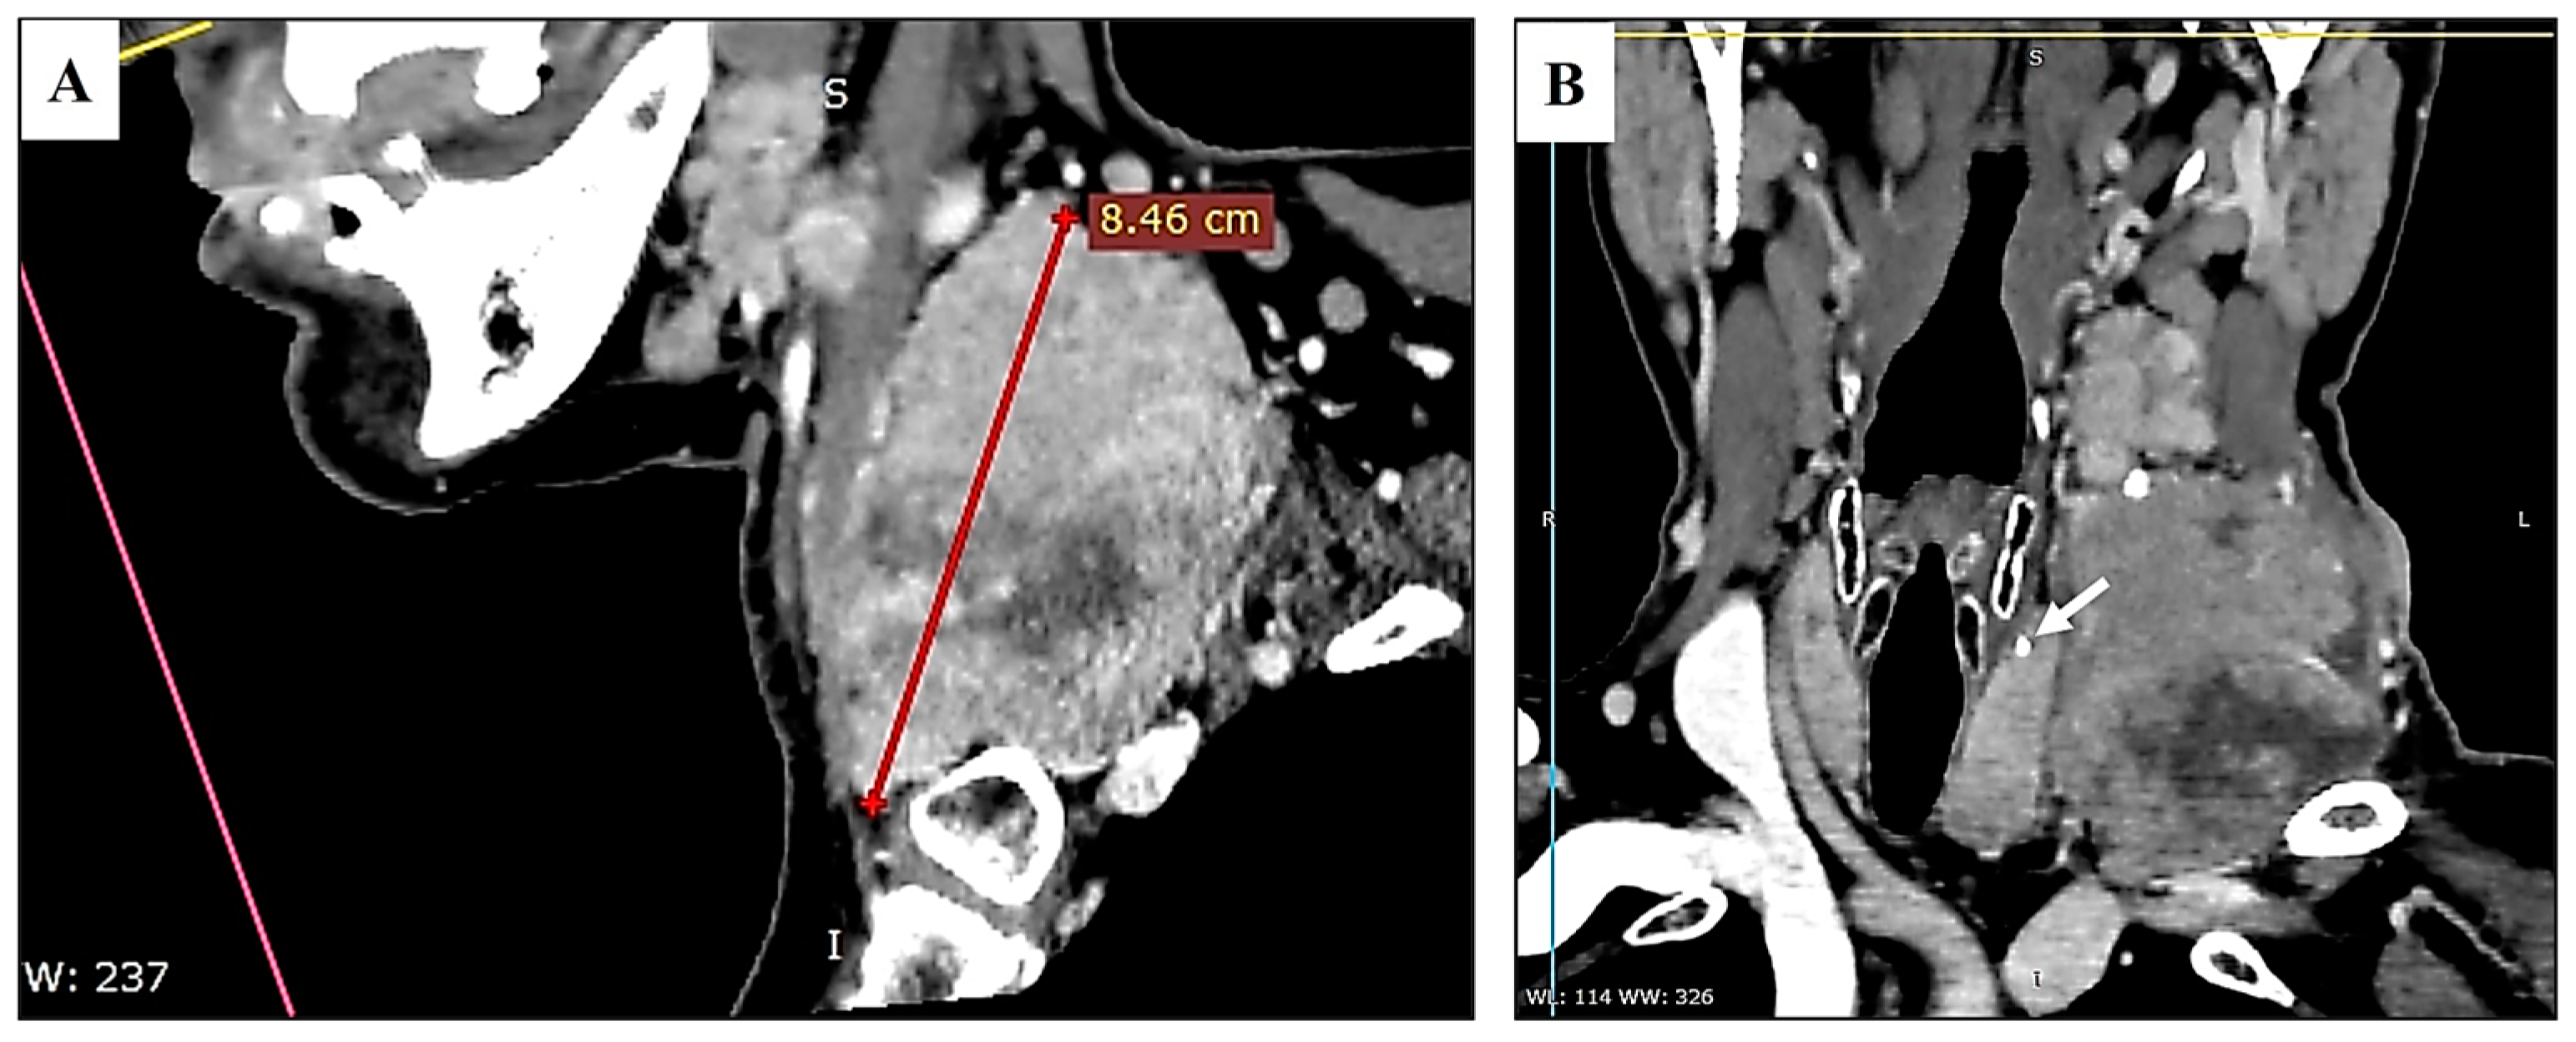

2. Case Presentation